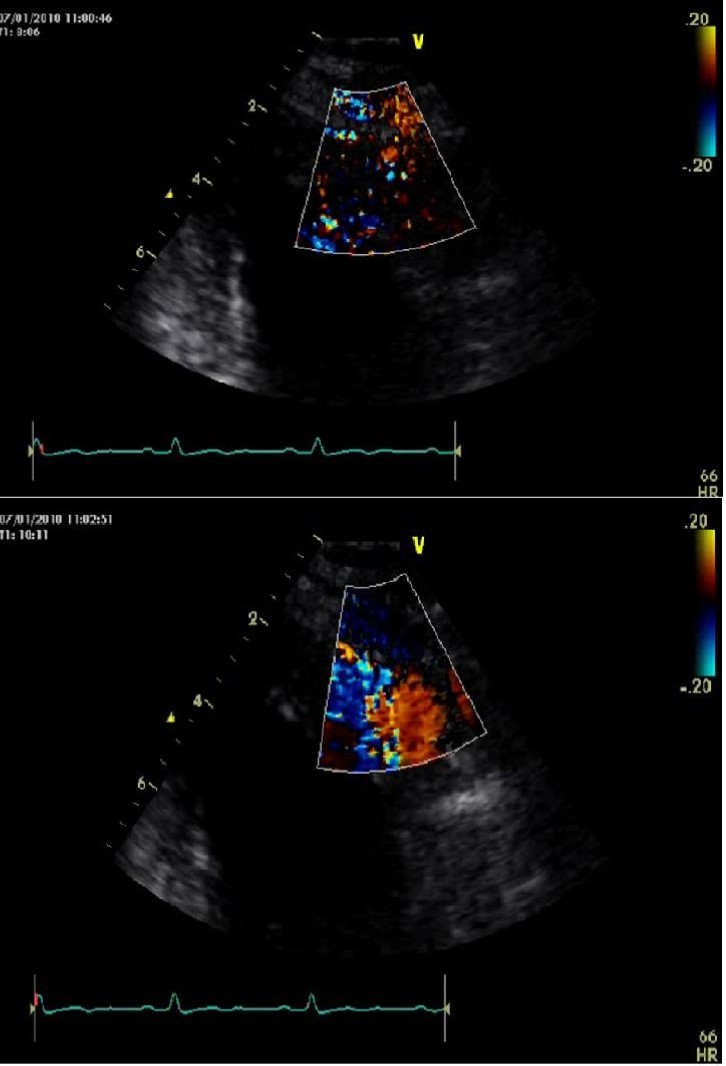

He was asymptomatic, in good general conditions, blood pressure 120/80 mmHg, no murmurs. The electrocardiogram showed sinus bradycardia (55 bpm) and left ventricular hypertrophy signs (deep and symmetric negative T waves in DI, aVL, V2 till V6). Echocardiogram (VIVID 7, 2-4 MHz probe) showed non classical apical hypertrophic cardiomyopathy (Figure 2), localized at anterior, lateral and posterior apex (septum was preserved), with no obliteration of apical cavity. By mean of color-Doppler evaluation, we observed multiple and thin color flows from LAD draining into apical region. Pulse-wave Doppler temporization was exclusively diastolic (Figure 3). Stress echocardiography with accelerate dipyridamole resulted negative for inducible ischemia and no variation in fistula flow was detectable. Inguinal hernia intervention was safely performed and the patient was advised to undergo periodical cardiologic controls.

Figure 3.Echo-color Doppler evalutation of left anterior descending artery fistula draining in left ventricular cavity